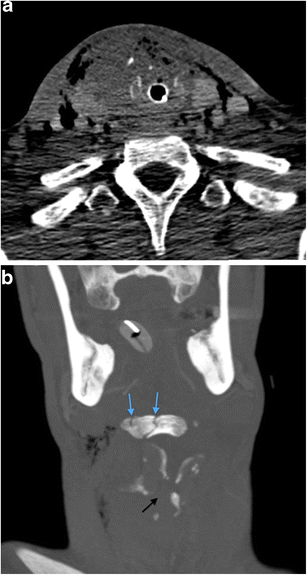

a Axial MDCTA image of a 38-year-old man who sustained a sharp penetrating injury to the midline zone 2 of the neck with a broken bottle (“glassing”). This particular mechanism is typically a combination of sharp penetrating and blunt laryngeal trauma. There is marked endolaryngeal, extralaryngeal and thyroid parenchymal haematoma, particularly on the right. Soft tissue emphysema can be seen outlining the pretracheal fascia which binds the thyroid gland. Further extensive soft tissue emphysema was demonstrated outlining the other deep cervical fascial layers, including the investing layer, the carotid sheath and the prevertebral/alar fascia layer (images not shown). Such extensive soft tissue emphysema should raise significant concern radiologically and clinically for penetration or perforation of the larynx. The patient has been successfully intubated. b Coronal-reformatted MDCTA image of the same patient as in a. Comminuted fracture disruption of the hyoid bone (blue arrows) and comminuted fracture-subluxation of the laryngeal cartilage (black arrow) are evident